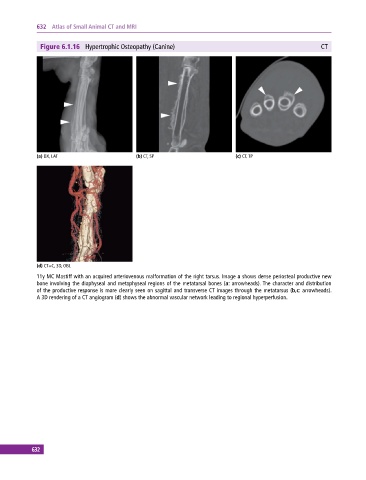

Figure 6.1.16 Hypertrophic Osteopathy (Canine) CT

(a) DX, LAT (b) CT, SP (c) CT, TP

(d) CT+C, 3D, OBL

11y MC Mastiff with an acquired arteriovenous malformation of the right tarsus. Image a shows dense periosteal productive new

bone involving the diaphyseal and metaphyseal regions of the metatarsal bones (a: arrowheads). The character and distribution

of the productive response is more clearly seen on sagittal and transverse CT images through the metatarsus (b,c: arrowheads).

A 3D rendering of a CT angiogram (d) shows the abnormal vascular network leading to regional hyperperfusion.